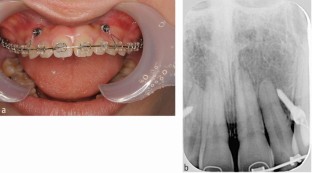

For orthodontic treatment, 0.018-inch standard edgewise brackets were bonded on the maxillary teeth. Two self-drilling TADs (diameter, 1.6 mm; length, 8 mm; Dual Top Auto Screw; Jeil Medical Corp, South Korea) were inserted into the buccal alveolar bone between the maxillary lateral incisors and canines to intrude the maxillary anterior teeth using an elastic chain. Before completion of opening the bite, positive crown torque of the upper incisors was achieved by torque moment generated with intruded force (Fig. 2A). After opening the bite, brackets were bonded on the mandibular teeth to create space between mandibular right central incisor and canine. However, after 12 months of intrusion, the crown of the maxillary right central incisor showed grey discoloration and a negative response to electric pulp tests (Fig. 2B). Furthermore, the patient reported severe spontaneous pain only in this tooth two days before visiting our clinic. However, no significant radiographic change was observed around the root apex of the maxillary right central incisor. Notably, moderate apical root resorption was observed in the maxillary right lateral incisor by the dental x-ray (Fig. 2C). From these symptoms, we thought traumatic pulp injury occurred on the right central incisor. Therefore, we removed the orthodontic force on the maxillary incisors with passive wire ligations between TADs and the upper canines, and 60 mg of loxoprofen sodium was administered three times a day for seven days. No more intrusion force to the upper incisors was applied because opening the bite had been completed. Six months after stopping orthodontic treatment, resolution of the crown discoloration was observed and the response to electric pulp testing was restored (Fig. 3A). Periapical radiography revealed a distinct radiolucency at the root apex (Fig. 3B). Two years after initiation of orthodontic treatment, the patient's gummy smile and overbite were corrected with a good intercuspal relationship. The missing mandibular right lateral incisor was replaced by direct bonding (Fig. 4A, Fig. 4B). Follow-up at four years after beginning of retention revealed stable smile aesthetics and tooth positions (Fig. 4C, Fig. 4D). Periapical radiographs showed marked root canal obliteration in the maxillary right central incisor and remodelling of the root apex in the maxillary right lateral incisor (Fig. 4E). The wire sequence used in this case is shown in Table 1.

(A) Intrusion of the maxillary anterior teeth using an elastic chain from temporary anchorage devices. (B) Intra-oral photograph 12 months after anterior teeth intrusion. The crown of the maxillary right central incisor showed discoloration. (C) Dental x-ray immediately after discoloration of the crown